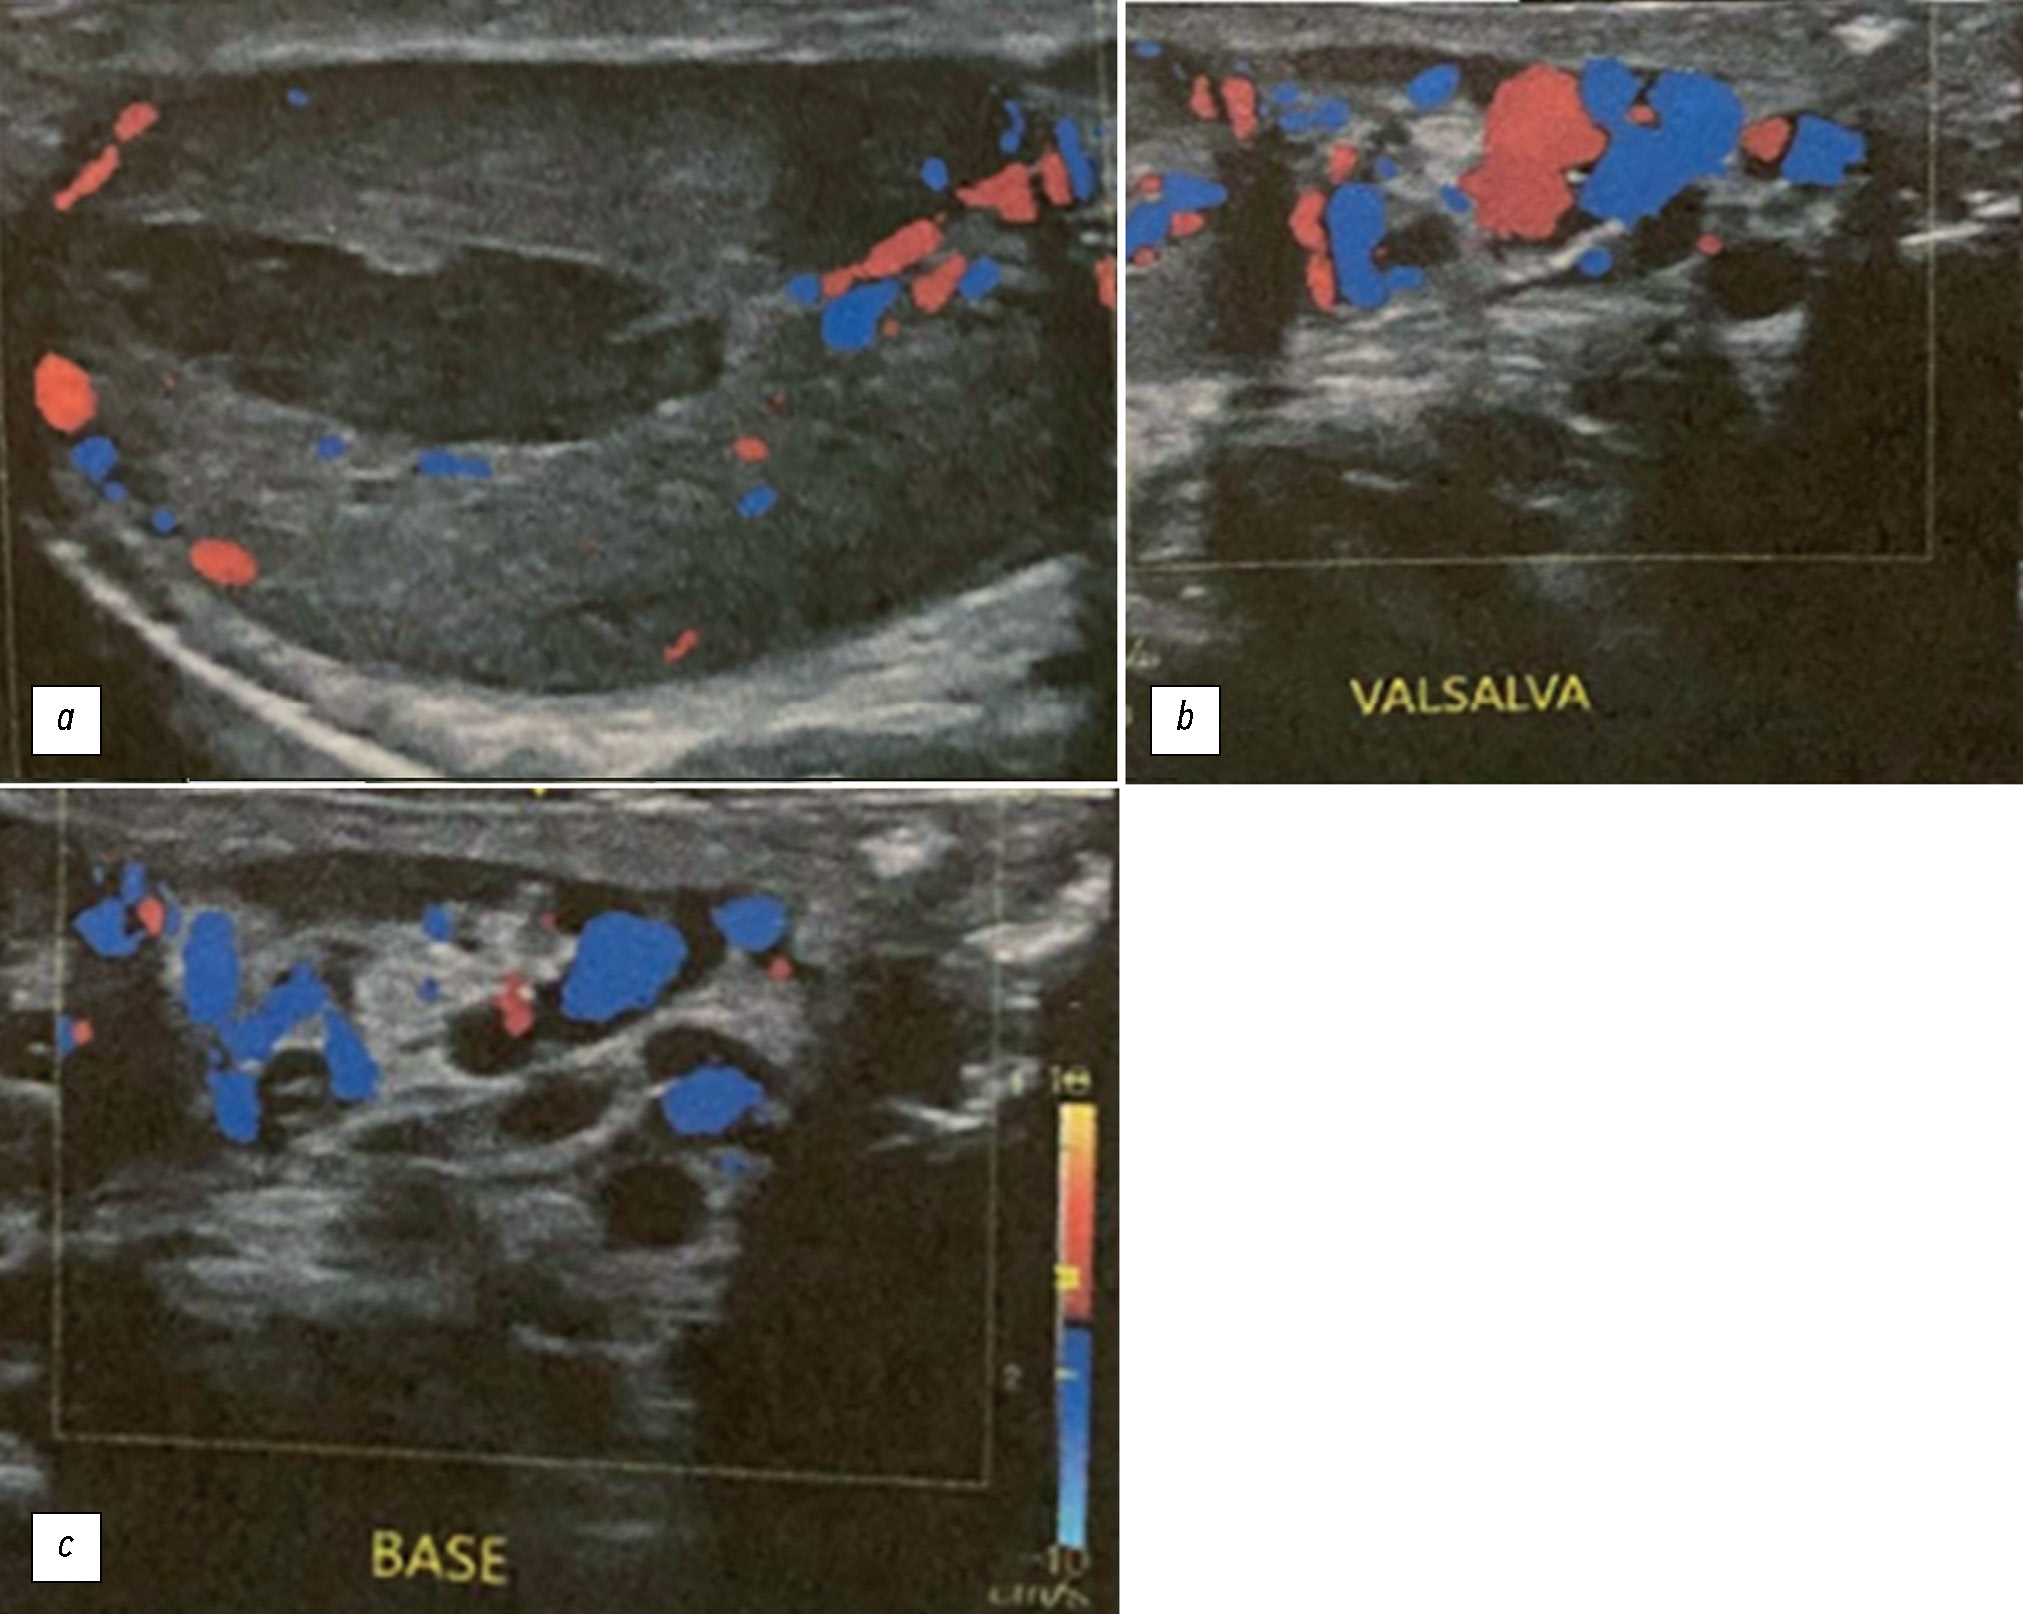

Несмотря на повышенную васкуляризацию яичка, цветовая допплерография (ЦДГ) данной области показала отсутствие кровотока в очаге поражения, в связи с чем возникли подозрения на инфаркт яичка. Кроме того, были выявлены признаки левостороннего варикоцеле II степени (рис. 2).

Рис. 2. По результатам цветовой допплерографии отмечено нарушение перфузии: отсутствие кровотока в очаге поражения и гиперваскуляризация по его периферии. Ипсилатеральный придаток яичка с отёчностью и неоднородной структурой отличается по эхогенности от контралатерального (a). Такую картину следует принимать во внимание при дифференциальной диагностике с небольшими опухолями, в которых зачастую отсутствует перфузия, однако морфология данных опухолей отличается от клиновидной. По результатам цветовой допплерографии перфузия в удлинённой овальной области ишемии отсутствовала. Нижние изображения представляют результаты эхокардиографии с цветовой допплерографией во время пробы Вальсальвы (b) и в исходном состоянии (c). Проведенное исследование дало одинаковые результаты.